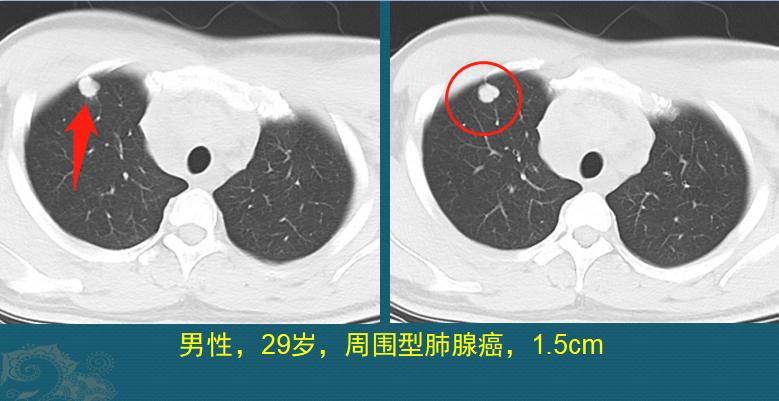

这位病人也是男性,不吸烟,才29岁,无意中摸到左侧颈部有个结节,比较硬,开始没有在意,结果1个月后右颈部也出现了结节,并且逐渐增大。

呼吸科医生摸了摸,默默给他开了胸部CT,发现1.5cm的肺癌:

这是一个不规则实性肺结节,表面有分叶,长径只有1.5cm,却已经发生了纵隔、颈部多发淋巴结转移,肩胛骨转移,没有手术机会了。

我们看下图箭头,这个结节是周围型,边缘贴近前壁胸膜,癌细胞顺着胸膜上丰富的淋巴管道漂流到纵隔、颈部淋巴结,鸠占鹊巢发展壮大了。右图箭头是明显增大的纵隔淋巴结,与大血管都分界不清了:

后来病人做了颈部淋巴结活检和基因检测,病理是中分化肺腺癌。